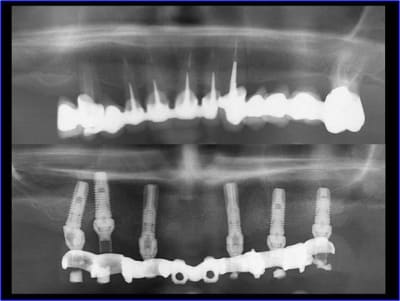

Pano de contrôle